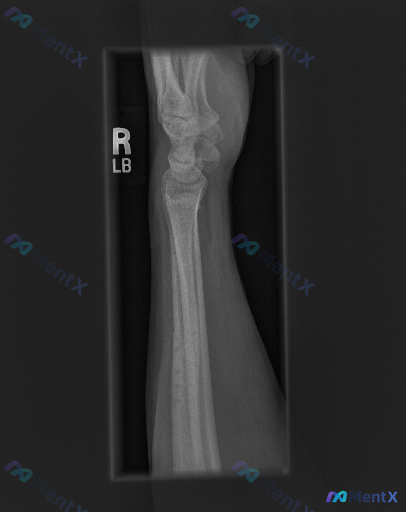

腕关节侧位X光片未见明确骨性异常,如果有症状,下一步判断重心该放哪?

整理到一则腕关节侧位X光片的影像观察资料,客观描述如下: - 骨骼方面:桡骨远端背侧、掌侧皮质轮廓清晰,未见明显皮质中断或台阶征;尺骨茎突及可见腕骨皮质连续;未见明显透亮骨折线、皮质裂纹、塌陷或骨小梁紊乱。 - 关节对位:腕骨排列符合生理曲线,未见明显月骨脱位/半脱位;头状骨轴线与桡骨长轴基本对齐;...

今天分享一个影像表现与症状主诉可能存在不一致的病例: 影像资料:右侧手腕正位X光片 影像分析结果: 1. 骨骼完整性:远端桡骨、尺骨及所有腕骨(舟骨、月骨、三角骨、豌豆骨、大多角骨、小多角骨、头状骨、钩骨)皮质连续,无骨折线、台阶感或骨小梁破坏; 2. 关节对位:桡腕关节、腕中关节及桡尺远侧关节(D...